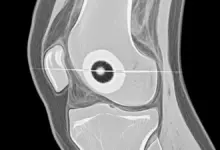

Entre os exames, radiografias podem mostrar alterações ósseas e sinais indiretos, mas a ressonância magnética geralmente é a principal para avaliar cartilagem, osso subcondral, edema ósseo e corpos livres.

Em casos selecionados, a tomografia auxilia no planejamento, principalmente quando se suspeita de fragmentos osteocondrais.